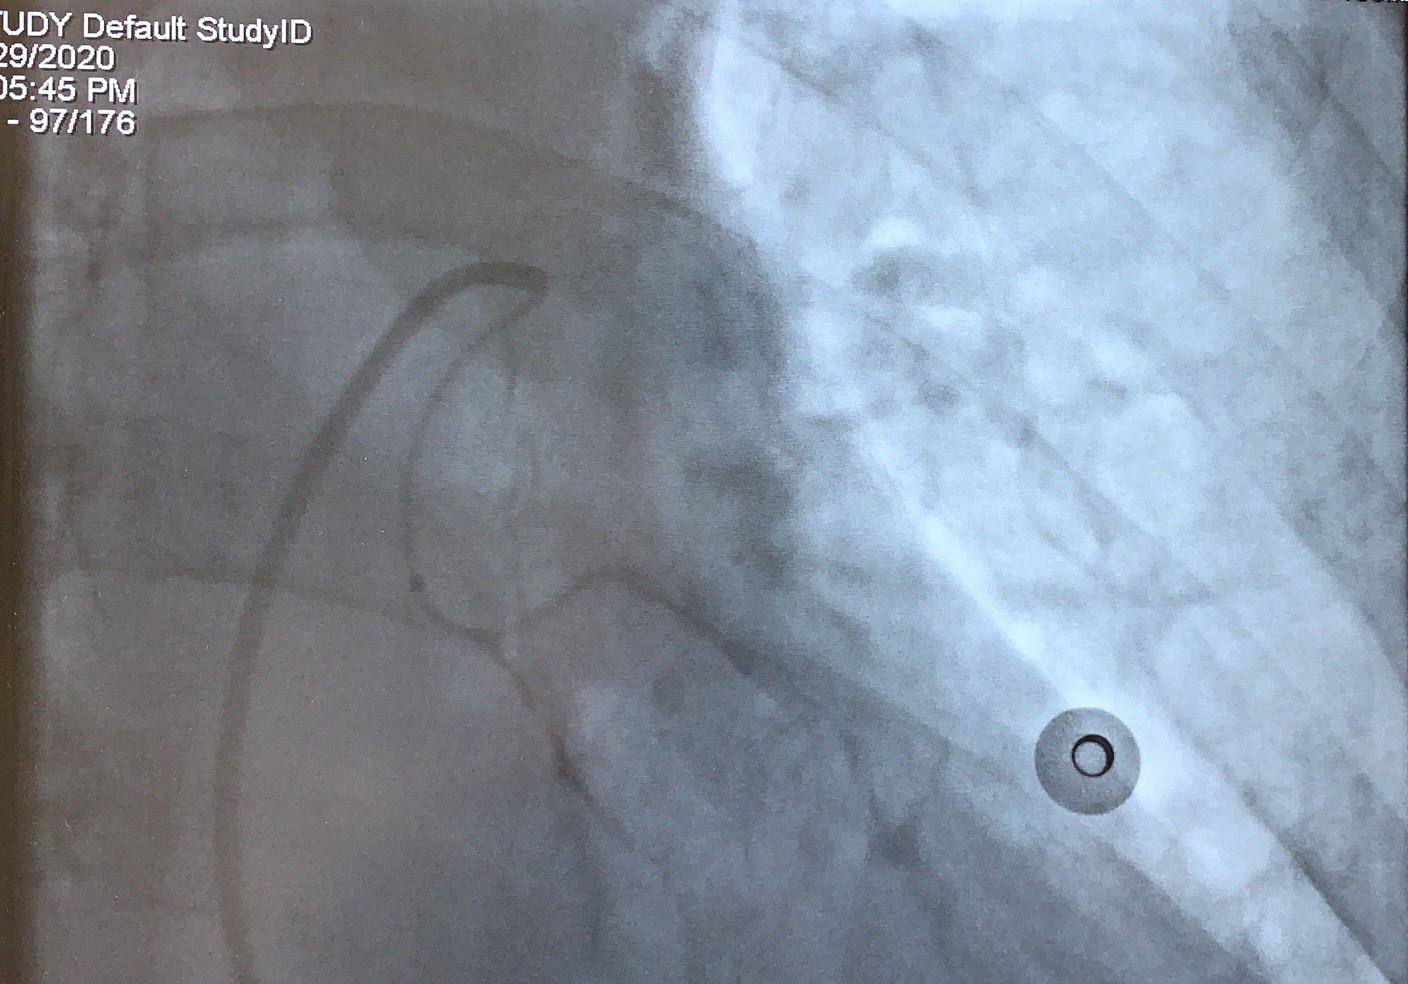

患者被送入介入治療室,術(shù)中造影發(fā)現(xiàn)雙側(cè)支氣管動(dòng)脈細(xì)小分支均破裂出血,予以選擇進(jìn)入后栓塞血管床,栓塞完后造影支氣管動(dòng)脈遠(yuǎn)端未見(jiàn)顯影。術(shù)后患者未再咯血,無(wú)特殊不適,無(wú)并發(fā)癥,手術(shù)成功。